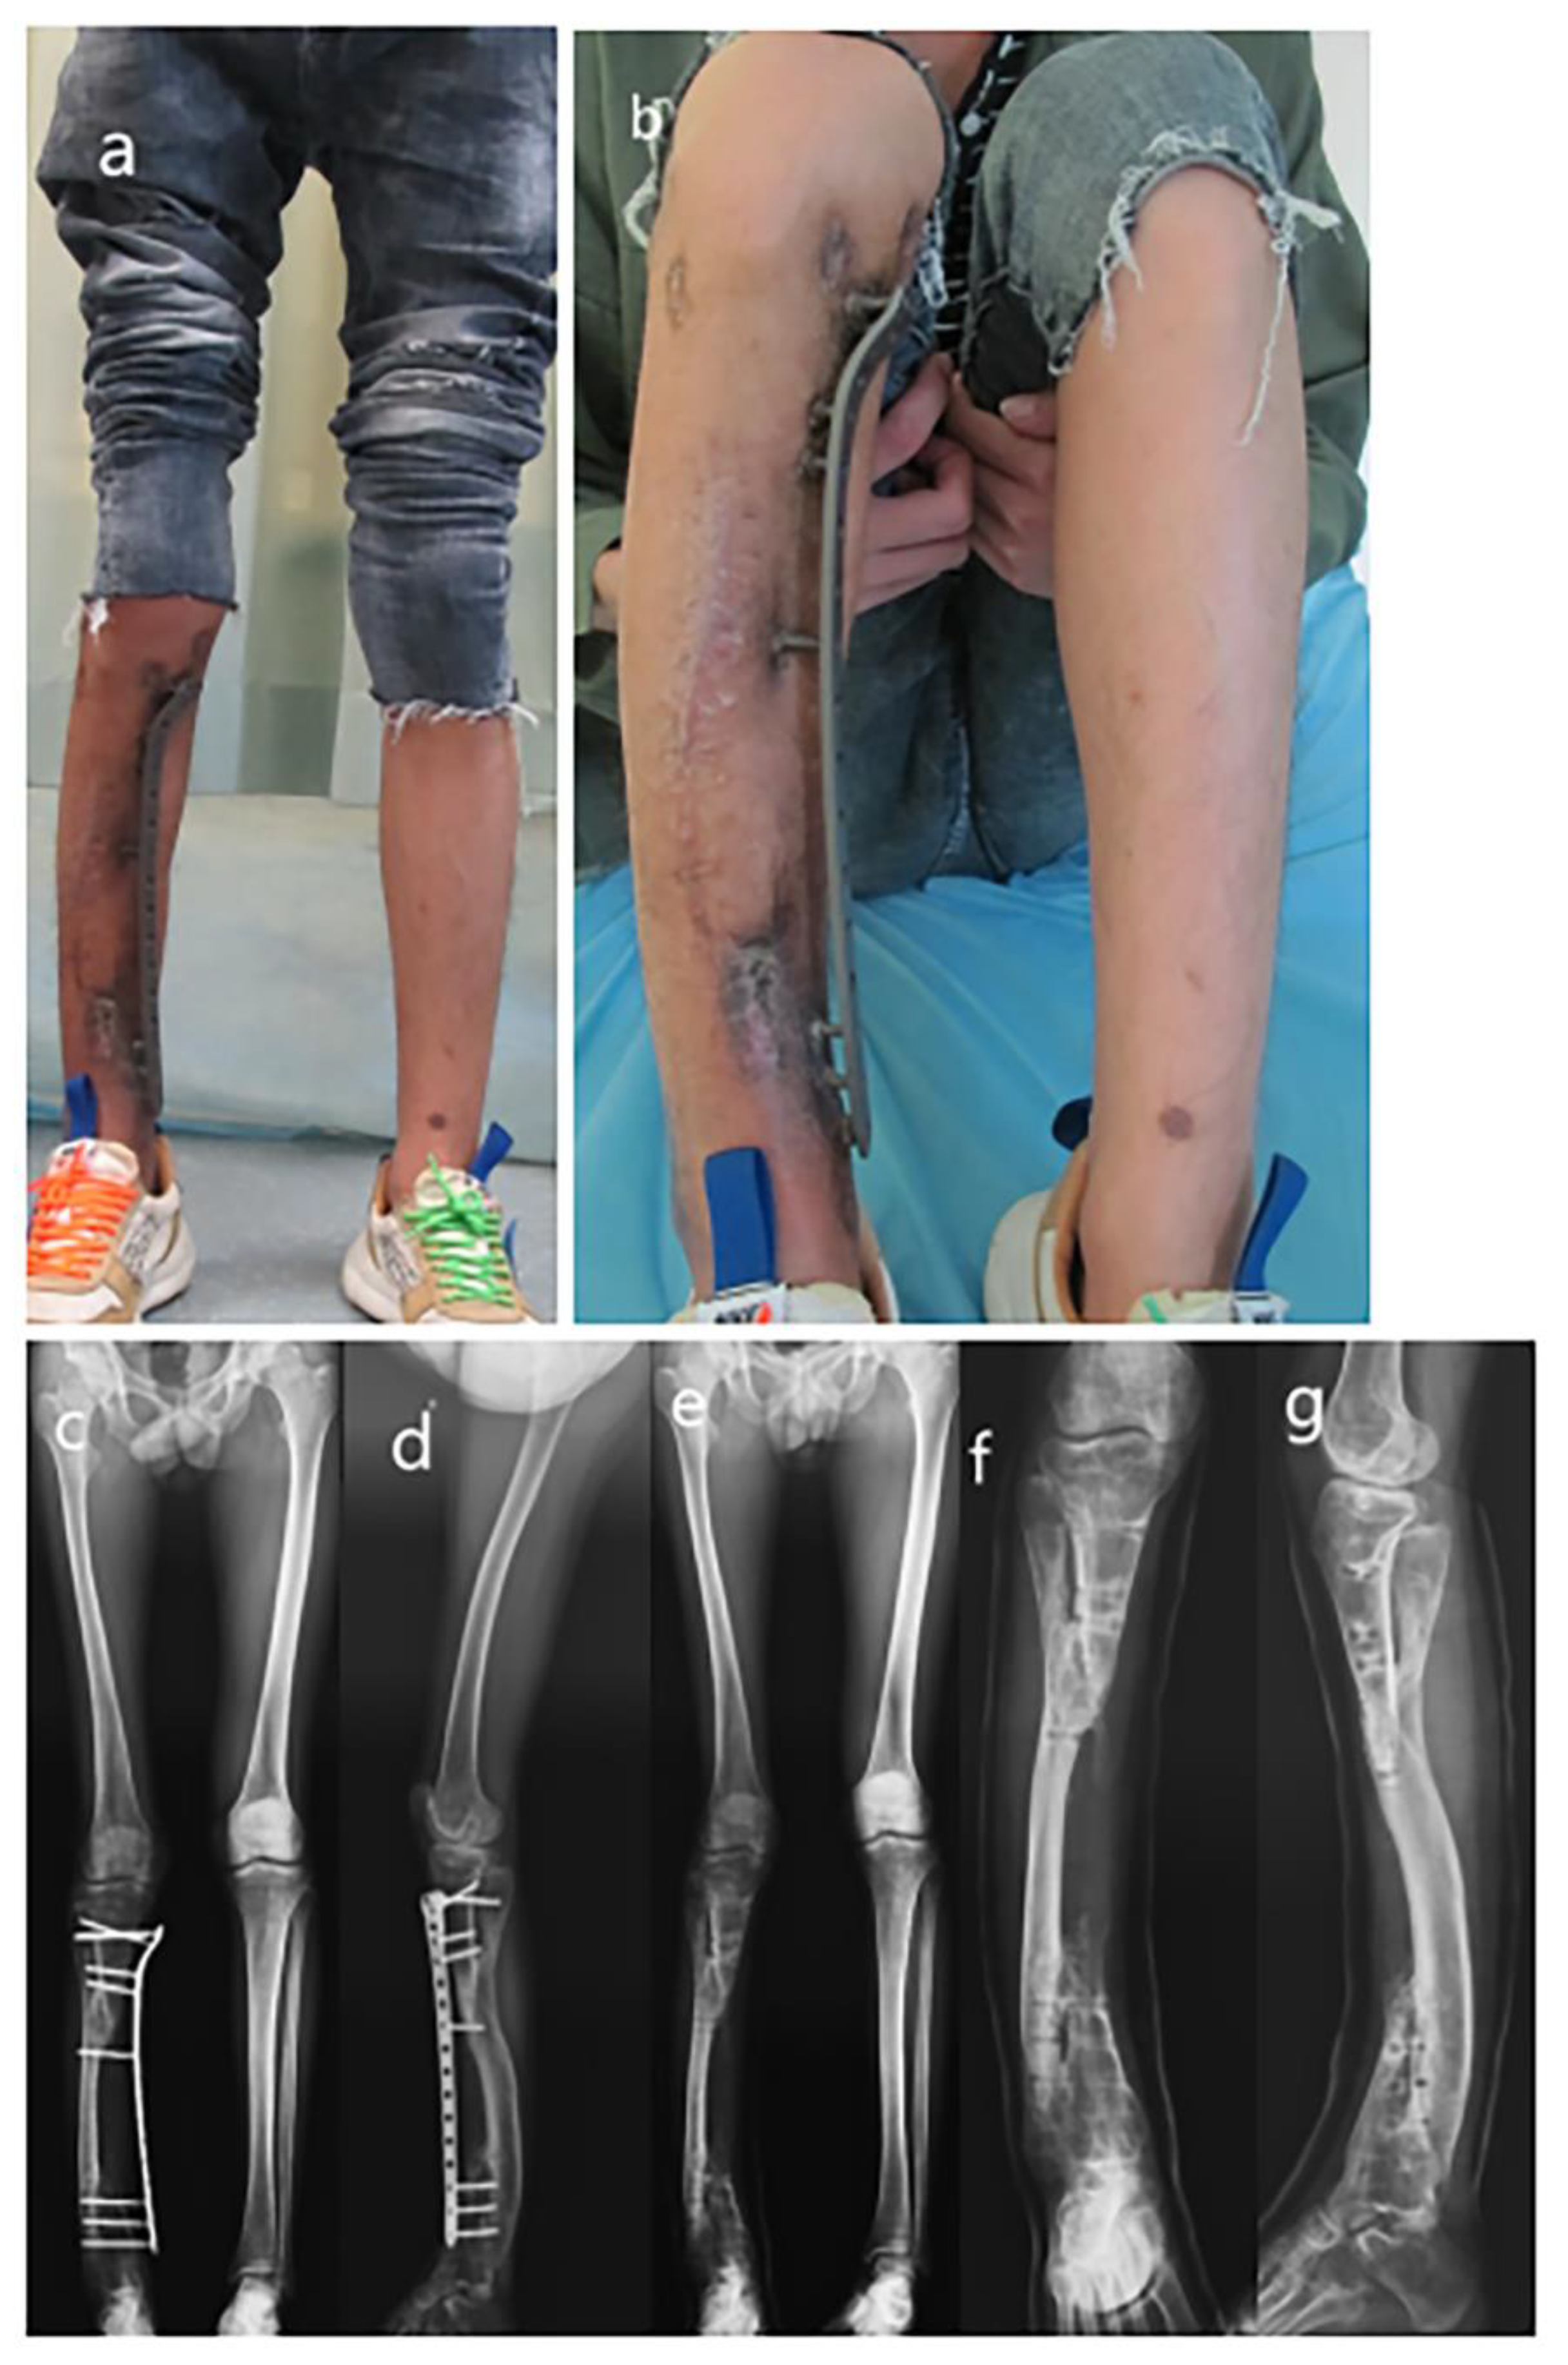

Figure 2.

Series radiographs of the lower extremity after Ilizarov apparatus instalment. (a) AP view radiograph of 5th-month follow-up; (b) AP view radiograph of 8th-month follow-up; (c) AP view radiograph of 9th-month follow-up; (d) Lateral view radiograph of 10th-month follow-up; (e) Lateral view radiograph of 5th-month follow-up; (f) Lateral view radiograph of 8th-month follow-up; (g) Lateral view radiograph of 9th-month follow-up; (h) Lateral view radiograph of 10th-month follow-up.